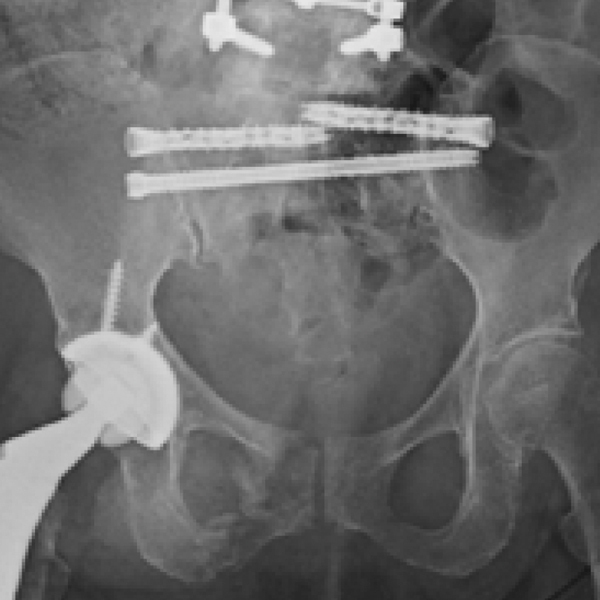

Sacral fracture fixation and bilateral SI joint fusion was performed.

- A single iFuse TORQ TNT™ implant was placed in the S2 corridor, spanning the sacrum and crossing both SI joints, addressing the left sacral alar nonunion and providing pelvic ring stability (Figs. 2-4).

- Percutaneous placement of bilateral iFuse TORQ® implants was performed sequentially, first at the left S1 and then the right S1, to provide additional sacral fracture fixation and to provide multiple fusion implants across the left and right SI joints.

Cunningham 1b